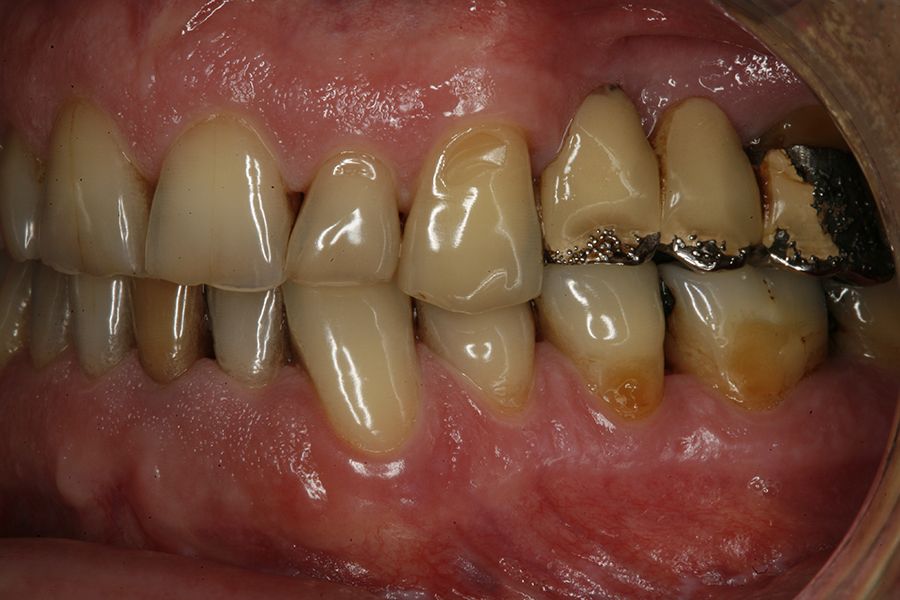

En las figuras 5-13 se muestra uno de los casos incluidos en el estudio.

En todos los pacientes se identificaron eventos adversos en sus rehabilitaciones con implantes, siendo estas complicaciones: fractura de la cerámica de la prótesis en un 63,6%, fractura estructural de la prótesis en un 18,2% de los casos (estructura en sí misma o recubrimiento de resina en las híbridas) y fracturas o fisuras en los implantes en un 18,2% de los casos. Las fracturas de las prótesis y de los implantes se vieron por igual entre hombres y mujeres, siendo la fractura de cerámica algo mayor en el grupo de los hombres (figura 1).

En cuanto al tipo protésico afectado por las complicaciones, fueron puentes de dos unidades en el 50%, seguido de coronas unitarias en el 36,4% y puentes de más de dos unidades en el 13,6% restante. El 77,3% de las prótesis que sufrieron complicaciones se encontraban cementadas y el 22,7% restante atornilladas, siendo más frecuente la

complicación en las prótesis cementadas en las coronas y puentes que en las prótesis completas, tal como vemos en la figura 3.